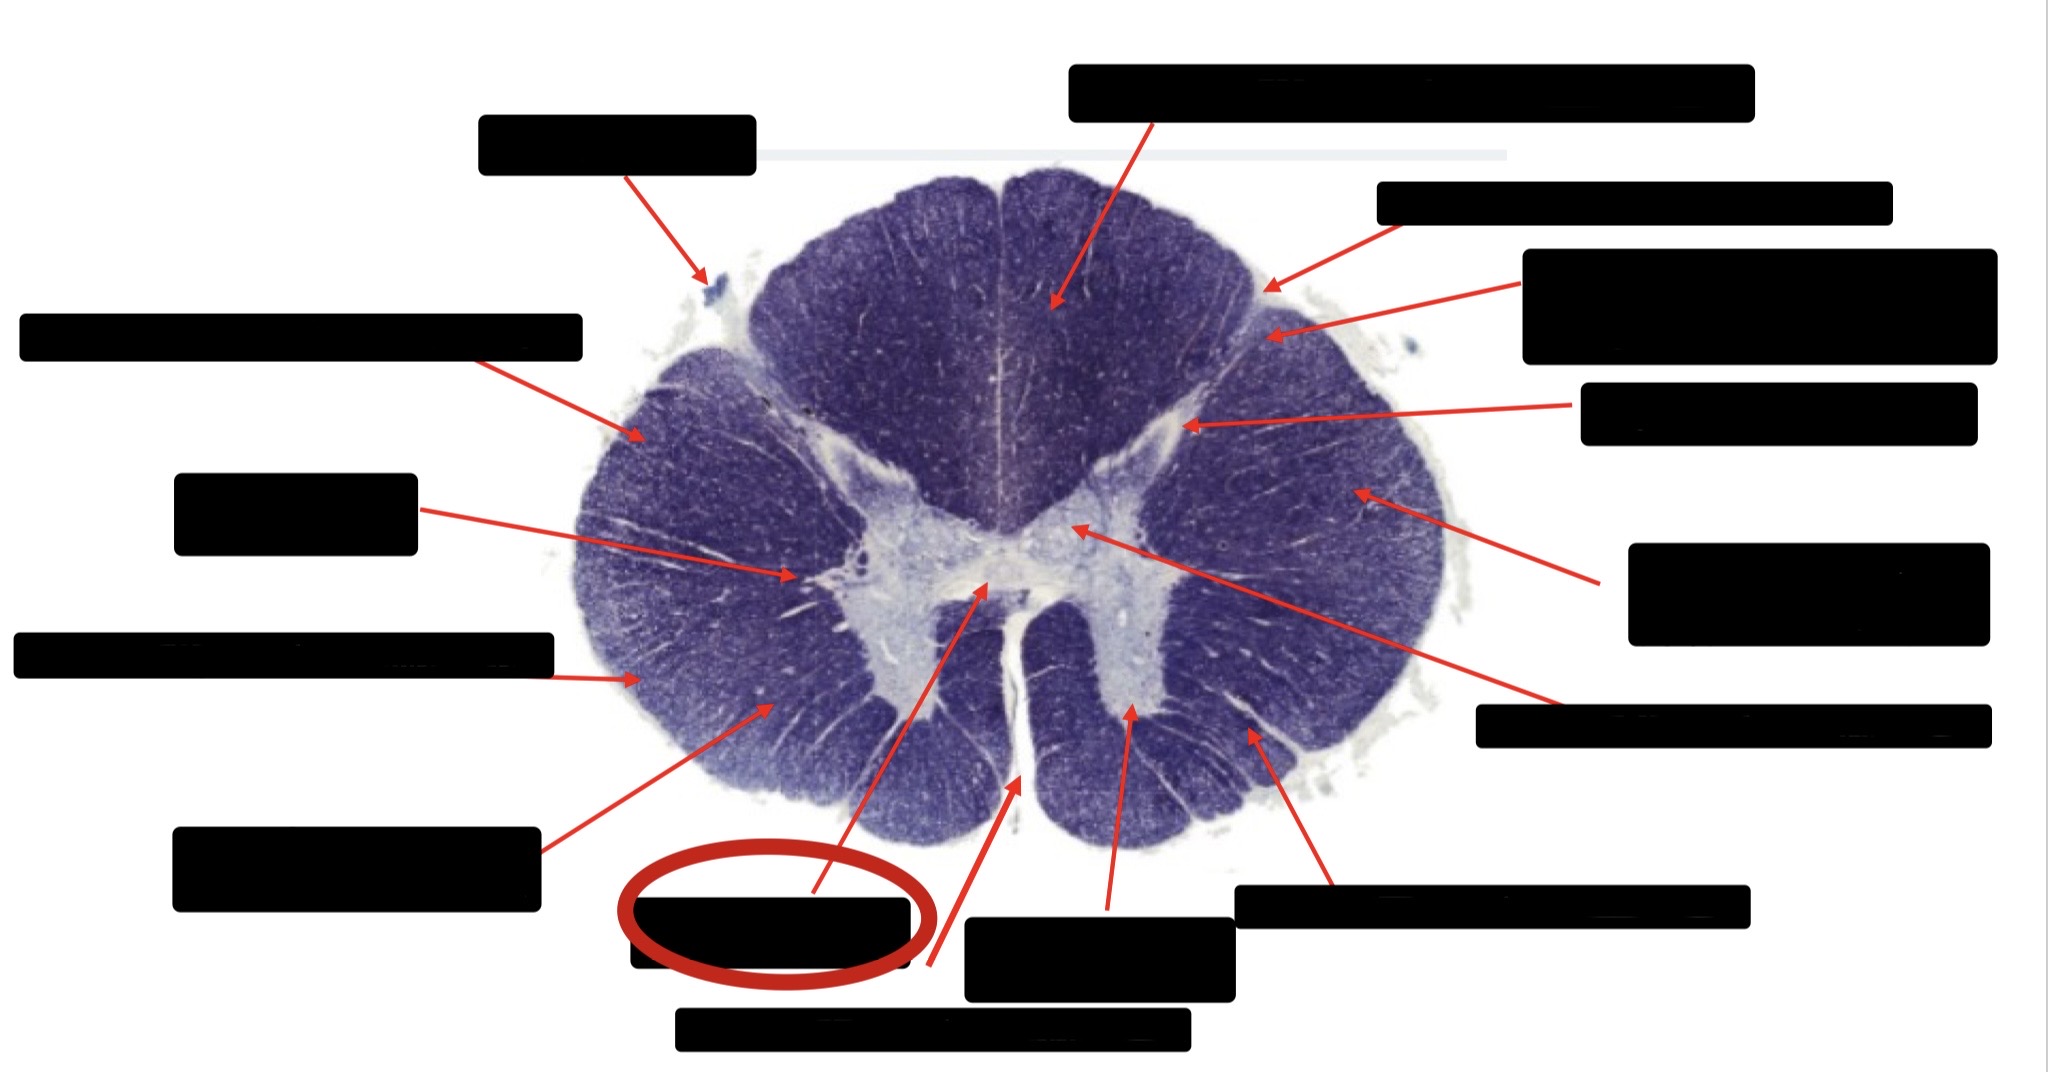

Anterior Spinal Artery

Denticulate Ligament

Ventral Root

Dorsal Root

Posterior Column Fasciculus Gracilis

Large Fiber Entry Zone

Central Canal

Dorsal Rootlet

Lissaeur’s Tract & Small Fiber Entry Zone

Substantia Gelatinosa

Lateral Corticospinal Tract

Anterior Horn Motor Neuron

Spinothalmic Tract

Anterior Horn Motor Neurons